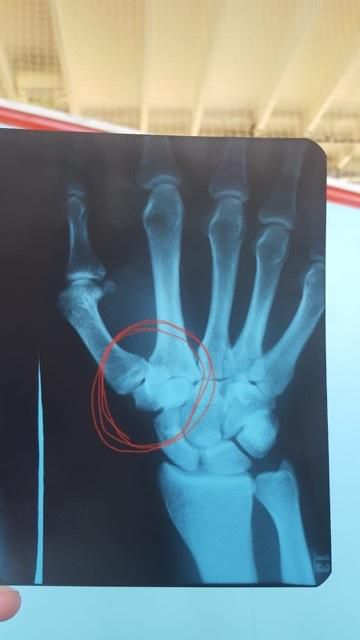

Dôvodom odloženia zápasu je zranenie šampióna druhej série šou Oktagon Výzva, Piráta Krištofiča. Tomu sa pri tréningu obnovilo staré zranenie ruky. Posilňovať a bezkontaktne trénovať síce môže, avšak na boxerské výmeny alebo jiu-jitsu váľanie na zemi to nie je.

"Je pravda, že Pirát má problémy s rukou. Trénuje a fyzicky je pripravený, ale nemôže boxovať, spárovať a biť sa. Zápas sa dnes po dohode všetkých ruší, ale diskutovali sme to už niekoľko posledných dní a všetci zainteresovaní boli informovaní. Fanúšikovia sa môžu tešiť na adekvátnu náhradu a dovolím si aj povedať, že najmenej rovnako atraktívneho súpera."